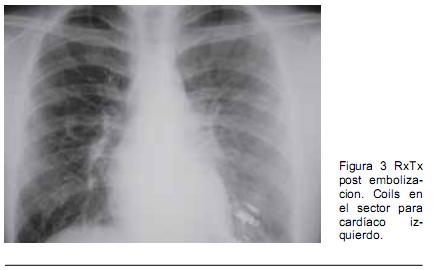

Hombre de 18 años con historia de epistaxis recurrentes y cianosis desde la infancia. Del examen clínico se destacaba: saturación arterial de oxígeno (SaO2) de 80%, mucosas hipercoloreadas e hipocratismo digital (Figura 1). La paraclínica confirmó poliglobulia e insuficiencia respiratoria severa, sin corrección con la administración de oxígeno. La RxTx evidenció una opacidad tenuemente homogénea en la región paracardíaca izquierda. El ecocardiograma descartó alteraciones estructurales. Se realizó angioTC con reconstrucciones 3D (Figura 2), confirmándose dos MAV, una de aspecto nodular, en el lóbulo superior del pulmón derecho, y otra más voluminosa, en la base del pulmón izquierdo (Figura 3). En esta última la arteria que la nutría continuaba la rama lobar inferior izquierda, siendo casi del mismo calibre y drenando en la vena pulmonar inferior. Se observaban múltiples dilataciones vasculares periféricas, bilaterales de aspecto varicoso. Se realizó embolización durante la arteriografía pulmonar con varios “coils” fibrilares de platino. La gasometría de control reportó una presión arterial de oxígeno (PaO2) de 79 mm Hg y una SaO2 de 96%.